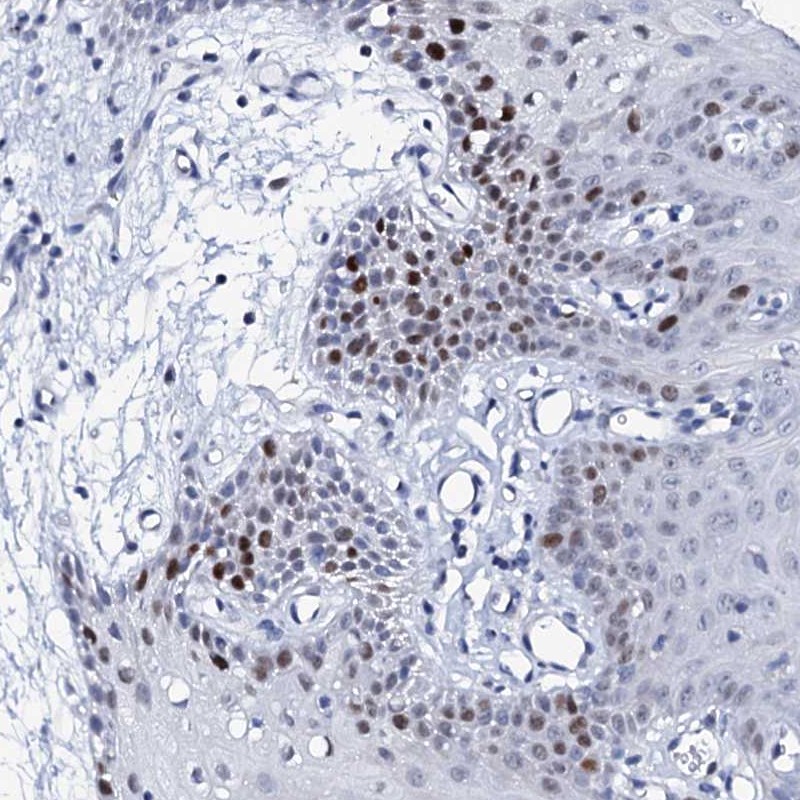

Immunohistochemical staining of human oral mucosa shows strong nuclear staining in a subset of cells in squamous epithelia.